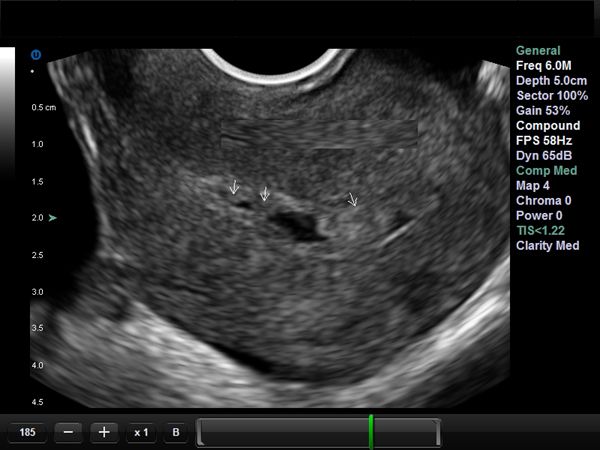

When this 32-year-old woman went for an ultrasound at 27-weeks into her pregnancy, a rare anomaly was found. Can you diagnose it?